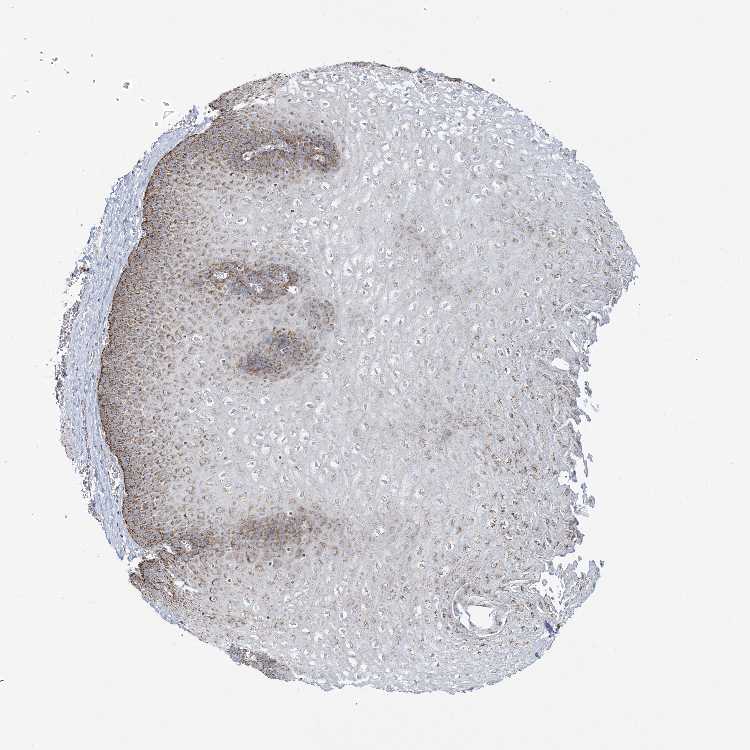

ESOPHAGUS - Antibody stainingi

Antibody staining in the annotated cell types in the current human tissue is reported as not detected, low, medium, or high, based on conventional immunohistochemistry profiling in selected tissues. This score is based on the combination of the staining intensity and fraction of stained cells.

Each image is clickable and will lead to virtual microscopy that enables deeper exploration of all samples and also displays staining intensity scores, fraction scores and subcellular localization as well as patient and tissue information for each sample.

Antibody HPA034537

Squamous epithelial cells High